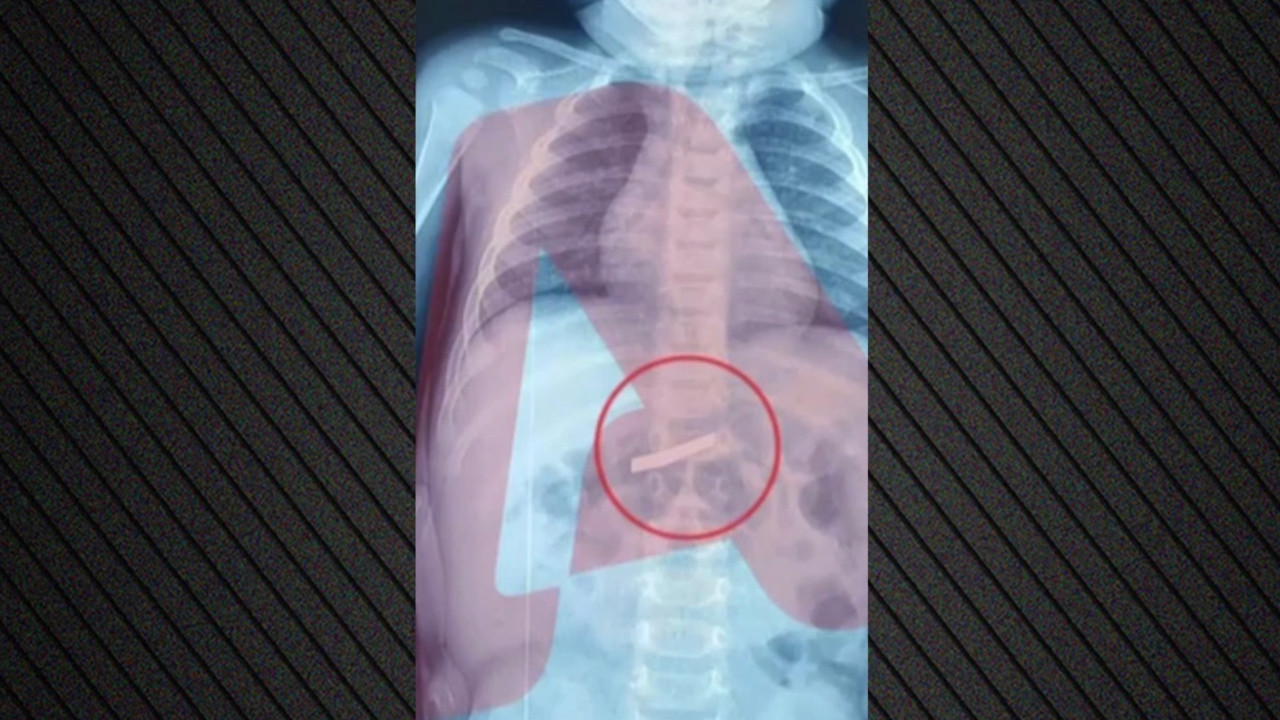

Etrafı koruma altında değildi. 1 hafta sonra özel uçakla Almanya'ya döndüm."‘DEMİR VAR AYAĞIMDA, SAKAT BIRAKTILAR'Olay yeriyle ilgili fotoğraf ve görüntüleri mahkemeye sunduklarını kaydeden Güray, "Ömrümü yediler, demir var ayağımda, sakat bıraktılar.

Ayağı keseceklerdi neredeyse.

Şu an kalıcı sakatlık var. 1 sene kendime gelemedim, 2 haftada bir ameliyata giriyordum.

Almanya'da 3 ay hastanede kaldım ve ayağımda yüzde 3'lük engel oluştu" diye konuştu.'O ÇUKURLARI 3 AY SONRA KAPATTILAR'Tazminat miktarını düşük bulan Yunus Güray, şunları söyledi:"Benim uçak masrafım sadece 22 bin avro tuttu. 9 yıl oldu, bir tane çukur değildi.